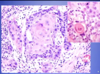

What pathology is shown in the provided image?

What features of the photos indicate this diagnosis?

Squamous cell carcinoma

L: ulceration & induration of the oral mucosa

R: malignant keratinocytes invading underlying connective tissue stroma & skeletal muscle